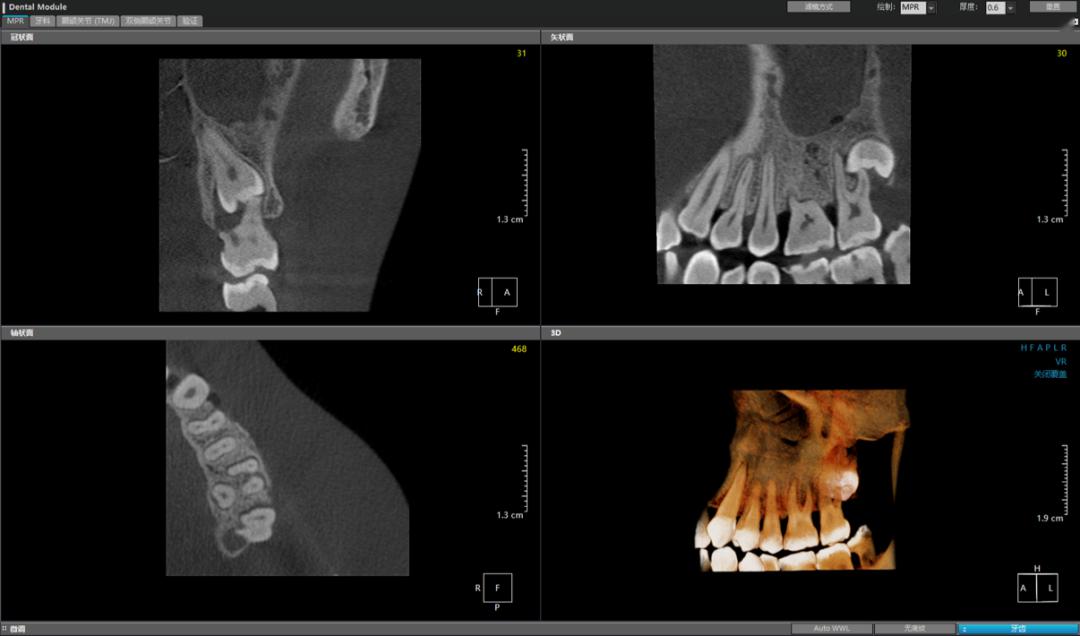

01 全方位细微切片,精准定位

最低70 μm体素 的小视野CT影像搭配OnDemand3D软件,超薄层厚影像触手可及,牙体牙髓诊疗更安心!

(图:伯爵新境界CT影像)